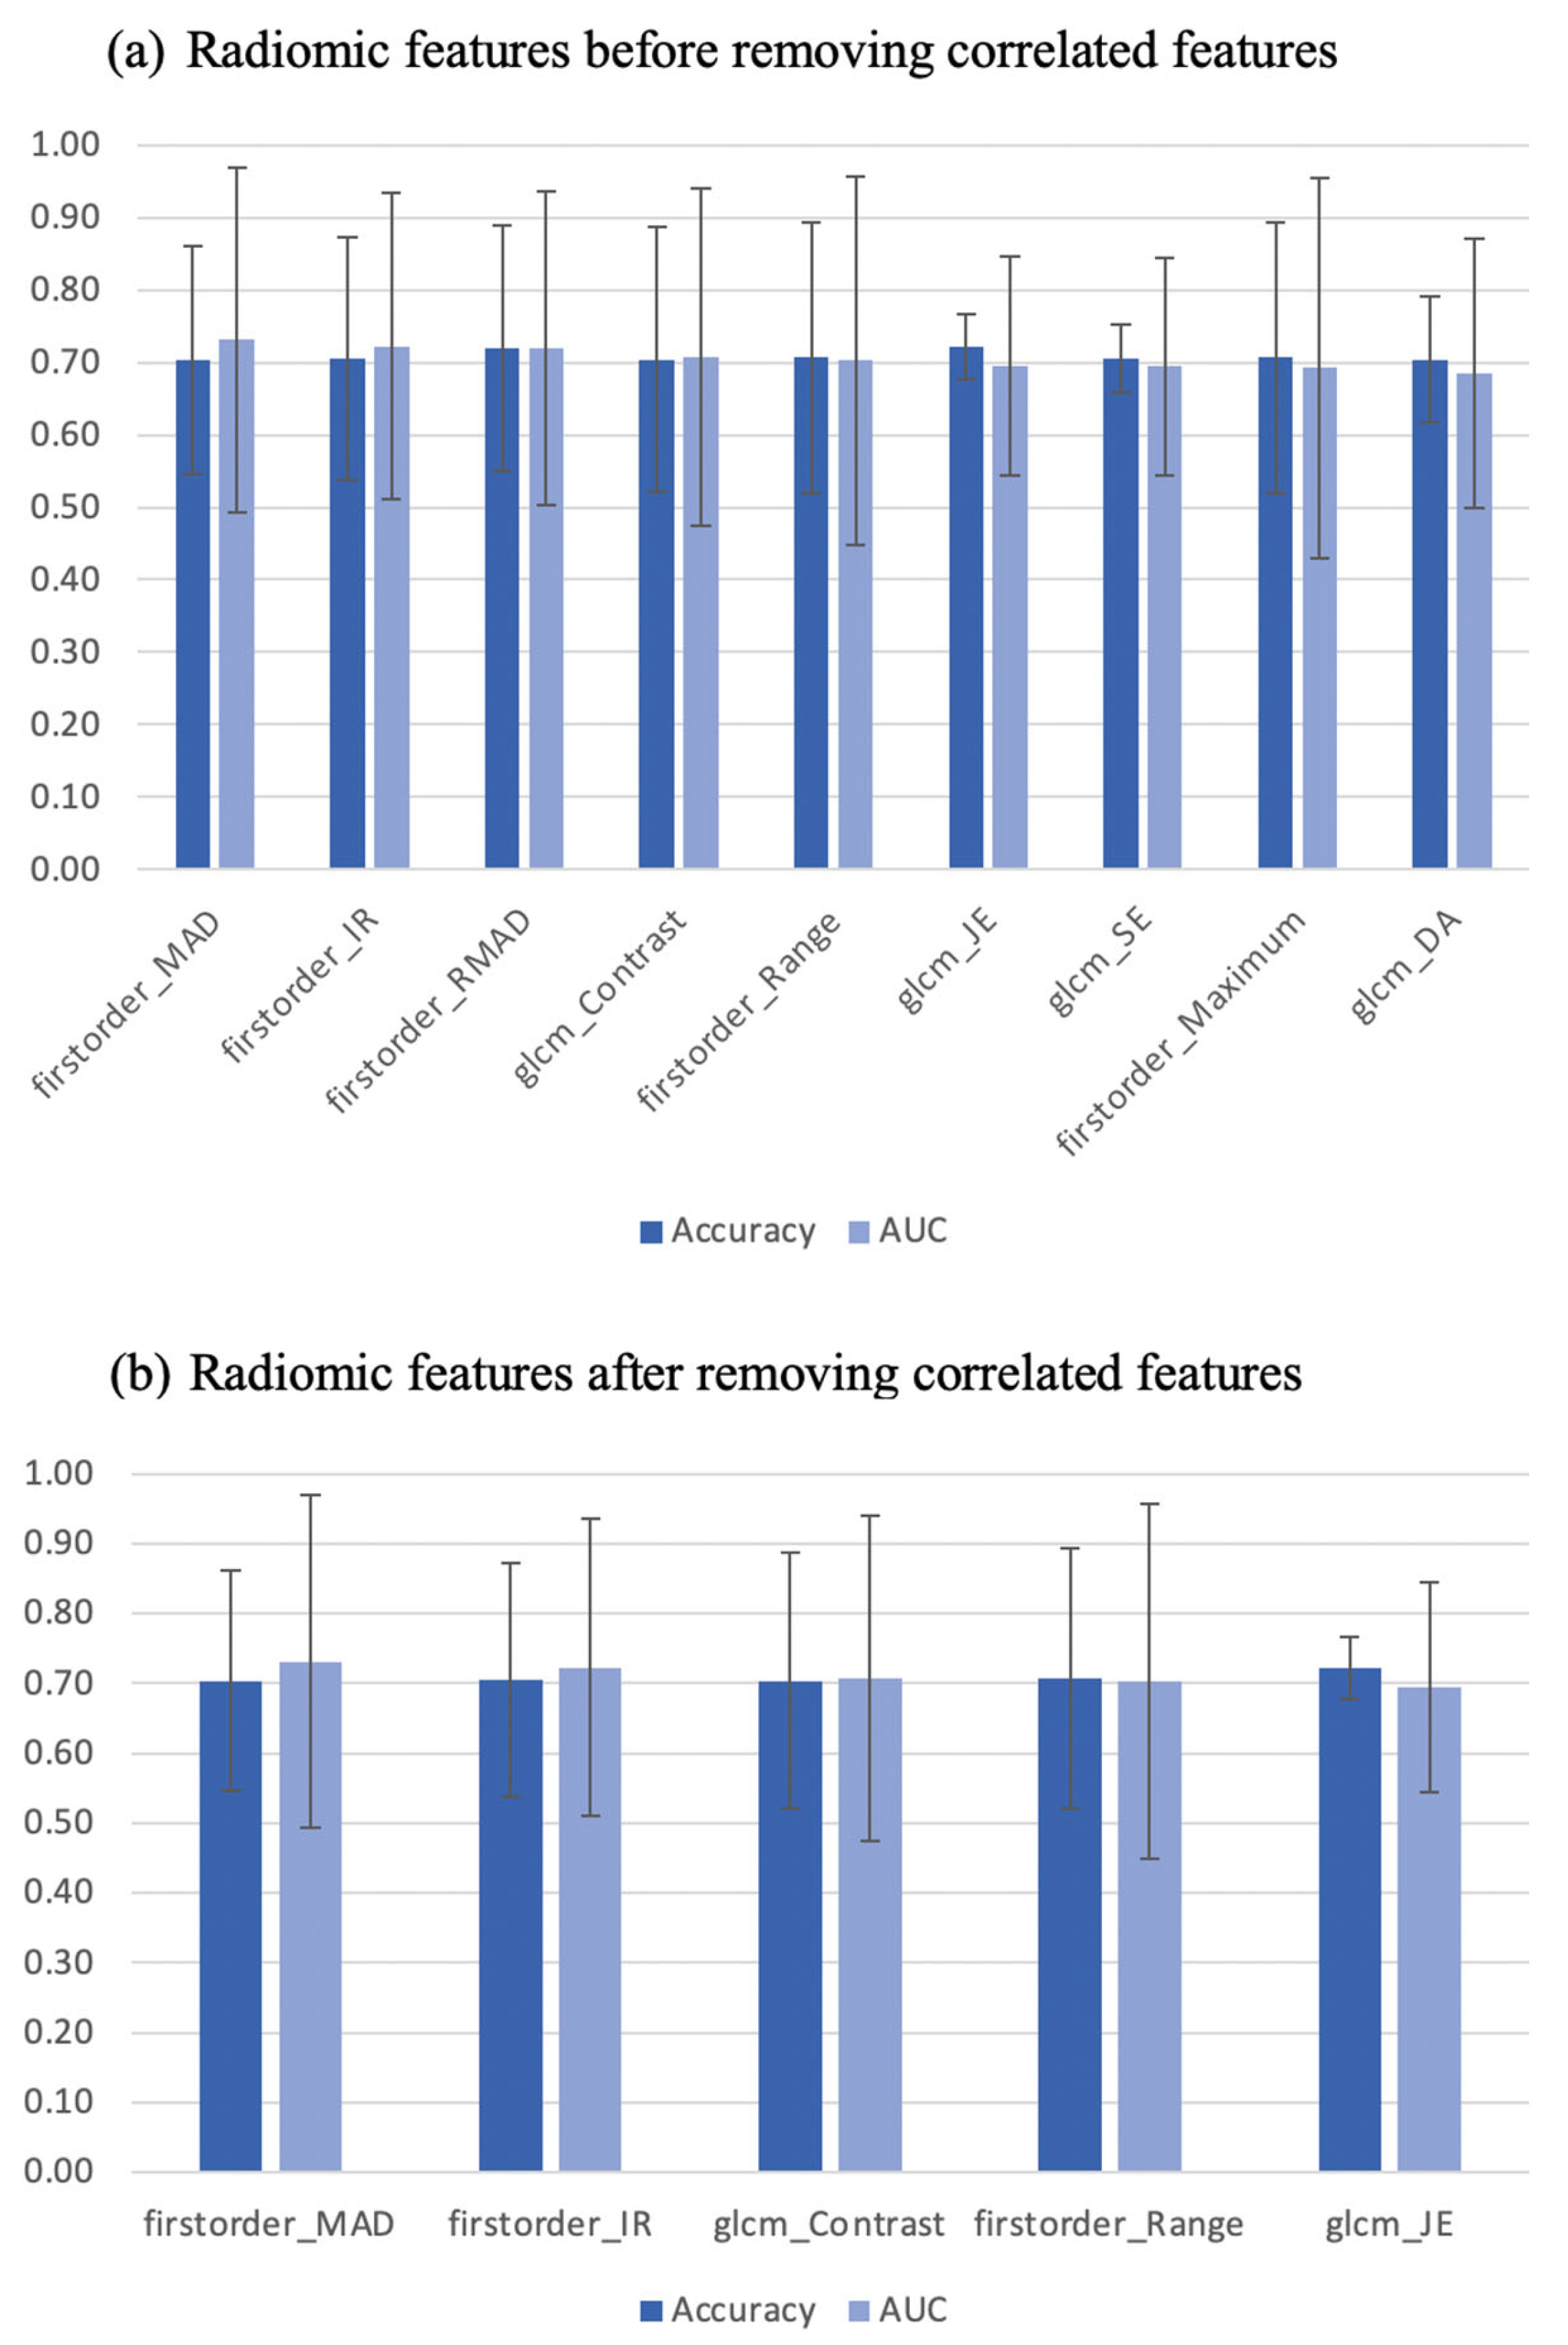

3.1. Individual Features—Diagnostic Utility

3.2. Signature Building and Machine Learning Performance